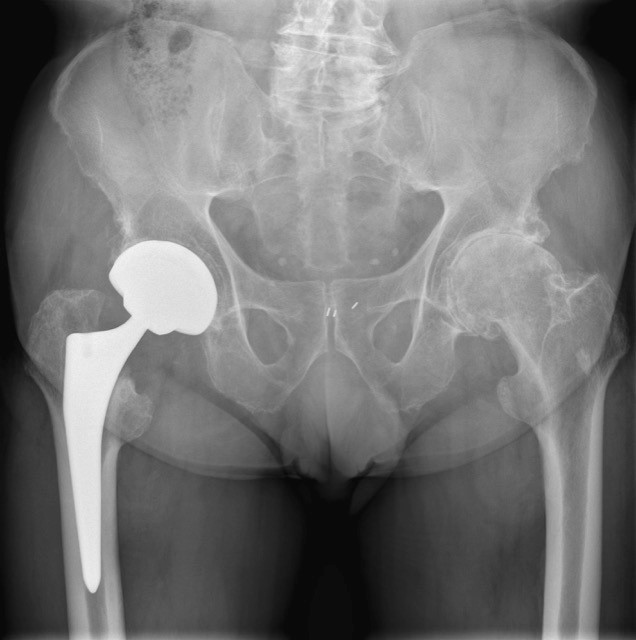

- Totale heupprothese

- Bij hoge verplaatste heupfracturen (in het gewrichtskapsel thv de heupnek)

- Ouderen met slechte botkwaliteit en actieve levensstijl

- Onmiddelijke steunname